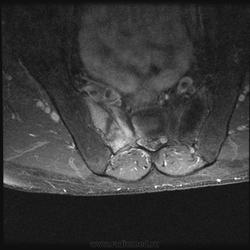

Мужчина, 60 лет. Направлен на МРТ пояснично-крестцового отдела позвоночника для исключения грыжеобразования. Жалуется на боли в правом тазобедренном суставе. Боли начались около месяца назад, сначала проявлялись в виде "неудобства", затем постепенно усиливались. В данный момент при объективном осмотре бережет ногу, хромает. Травмы, воспалительные заболевания отрицает.

При МРТ пояснично-крестцового отдела обратил на себя внимание крестец. Досмотрели крестец с контрастом. Хотелось бы услышать Ваше мнениие по поводу представленных снимков:

А по текущему случаю предложения будут? Не смущает ли кого-нибудь неровный косо-вертикальный гипоинтенсивный сигнал, в особенности заметный на постконтрастных корональных изображениях?